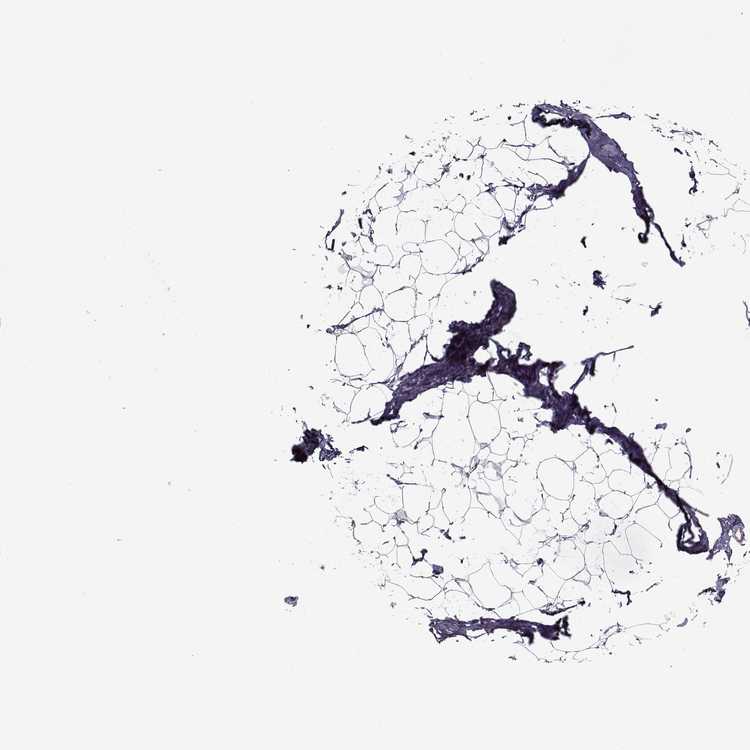

TISSUE PRIMARY DATA BREAST Show tissue menu

BREAST - Antibody stainingi

Antibody staining in the annotated cell types in the current human tissue is reported as not detected, low, medium, or high, based on conventional immunohistochemistry profiling in selected tissues. This score is based on the combination of the staining intensity and fraction of stained cells.

Each image is clickable and will lead to virtual microscopy that enables deeper exploration of all samples and also displays staining intensity scores, fraction scores and subcellular localization as well as patient and tissue information for each sample.

Antibody HPA001895Antibody CAB000053Antibody CAB078160

Adipocytes Not detectedHighNot detected

Glandular cells Not detectedNot detectedLow

Myoepithelial cells Not detectedHighNot detected